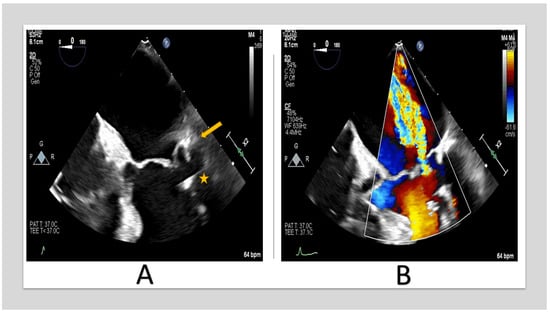

Extension of the posterior annulus calcifications to the posterior leaflet and sub-valvular apparatus resulting in restricted motion of the posterior leaflet and, therefore, lack of coaptation [21] (Figure 2).

Figure 2.

TEE images of 67-year-old woman with severe MR. (A) shows posterior annulus calcification (arrow) with sub-valvular apparatus extension (star. (B) shows posteriorly directed MR jet due to posterior leaflet restriction. (TEE: transesophageal echocardiography, MR: mitral regurgitation).